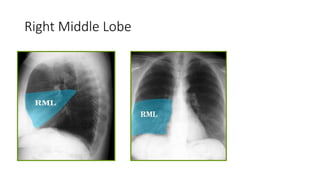

Right Middle Lobe

Right lower Lobe